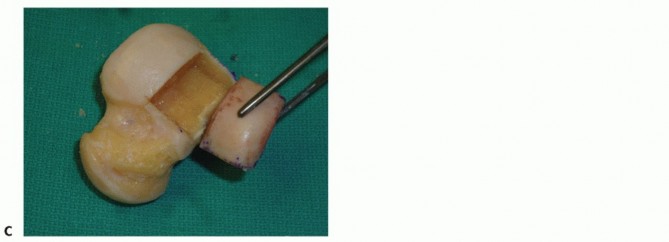

- TECH FIG 2 • (continued) C-E. Excision of the talar shoulder lesion using the microsagittal and oscillating saws. F. Talar shoulder lesion removed.

Excise the diseased portion of the talus (TECH FIG 2C-F).

Reciprocating and microsagittal saw (use cool saline to limit risk of heat necrosis) May need a small curette and rasp as well

Define the dimensions of the recipient site. Use a caliper and a ruler and double-check the measurements. - Harvesting Graft from Donor Talus

Carefully mark the dimensions for graft harvest on the allograft (TECH FIG 3A).

Same location on the allograft talus as the recipient site on the native talus

If you err, err to have the graft slightly too large. Be sure to account for saw blade thickness. “Measure twice and cut once.”

You have only one opportunity, so be sure the measurements and orientation of the saw blade for each cut are optimal.

The allograft can be stabilized with two large pointed reduction clamps (TECH FIG 3B).

Extract the graft from the donor talus (TECH FIG 3C).

- TECH FIG 3 • A. The dimensions of the recipient site are carefully recorded and transferred to the allograft. B. Two pointed reduction clamps are used to stabilize the allograft during preparation. C. Donor allograft with newly prepared graft removed.